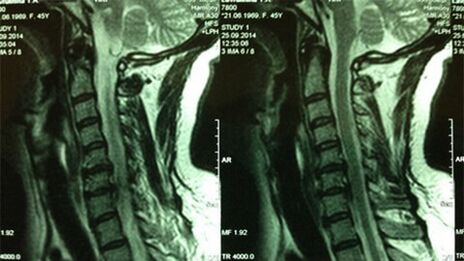

- Emakakaelaosakonna X -RAY; Protsessi algfaasis on emakakaelaosakonna MRT informatiivsem - see tagab tahkete ja pehmete kudede kõrgekvaliteedilise visualiseerimise -, mis näitab ümbermõjudevaheliste ketaste seisundit, osteofüütide olemasolu, deformatsioonid, närvijuurte ja veresoonte kahjustused; hindab sidemete, lihaste, luukoe seisundit;